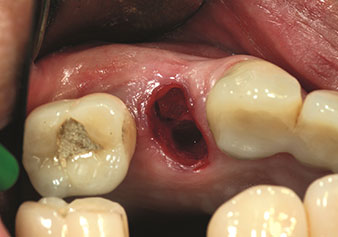

Indikation Interner Sinuslift

W&H bietet auch die perfekte Lösung für den internen Sinuslift an Nach der Kieferhöhlenpräparation mit dem

entsprechenden Instrumentarium (Abb. 3) erfolgt mit dem neuen Instrument Z35P (Abb. 4) die hydrodynamische Abhebung der Membran. Mit dem gleichen Instrumentenset kann auch die Implantatbett-Aufbereitung piezochirurgisch in aufsteigenden Durchmessern erfolgen (Abbildung drei und vier mit freundlicher Genehmigung von Dr. Mario Kirste, Frankfurt/Oder).

Präparation des Kieferhöhlenbodens und zum Anheben der Schneider'schen Membran mittels Kühlmedium (Instrument Z35P)

Abb. 4: Präparation des Kieferhöhlenbodens und zum Anheben der Schneider'schen Membran mittels Kühlmedium (Instrument Z35P). Foto: © Dr. Mario Kirste (Frankfurt / Oder)